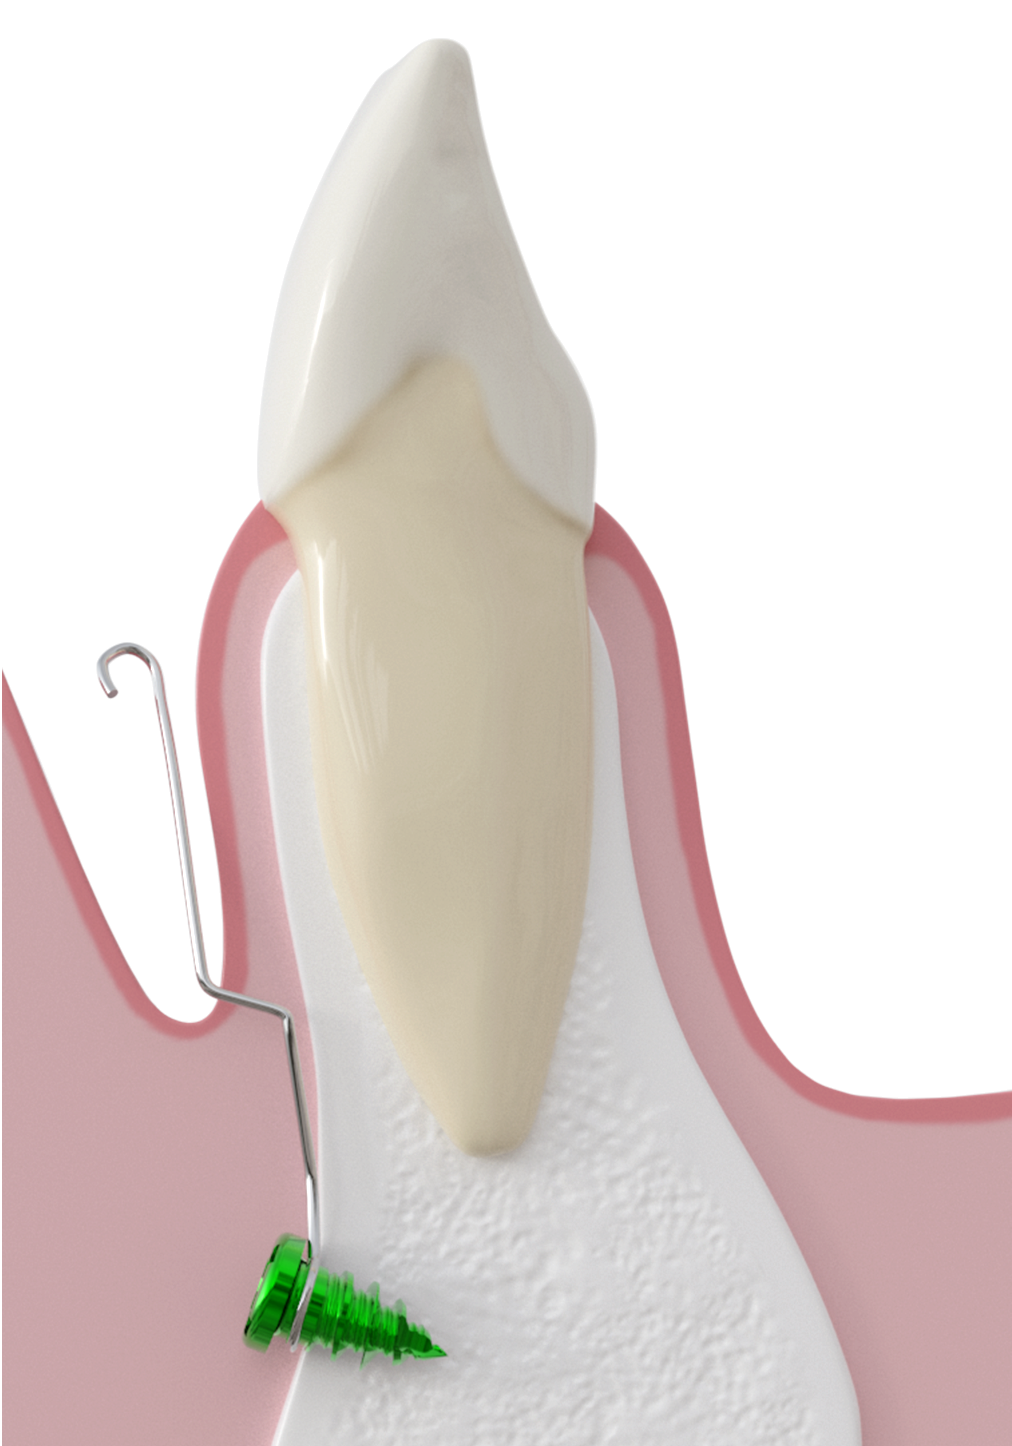

- une ou deux micro-vis en alliage de titane TiAl6V4, autoforeuse et autopréhensible sur le tournevis dédié, enfouie en fond de vestibule au-delà des apex

- une connectique en alliage CTnox spécialement conçu et développé pour le système CT8, attachée à la vis et émergeant au centre du vestibule dans une muqueuse non kératinisée. Le fil est plaquée contre la corticale osseuse sous la muqueuse et au delà il longe la gencive ce qui en fait un dispositif très discret et faiblement invasif pour le patient.

- Vissage de la ou des vis et plaquage du fil contre la corticale osseuse

Le geste peut être réalisé quasiment en aveugle car il n’y a aucun risque anatomique pour les structures sous-jacentes.

- Réalisation d'une baïonnette au niveau du trait d'incision (fond de vestibule)

En deçà, le fil est plaqué contre l’os, au-delà il doit longer la gencive sans appui.

Elle est réalisée à l’aide de l’instrument dédié dont la gorge coiffe le fil et qui est tourné d’ un huitième à un quart de tour environ afin de compenser l’épaisseur de muqueuse.